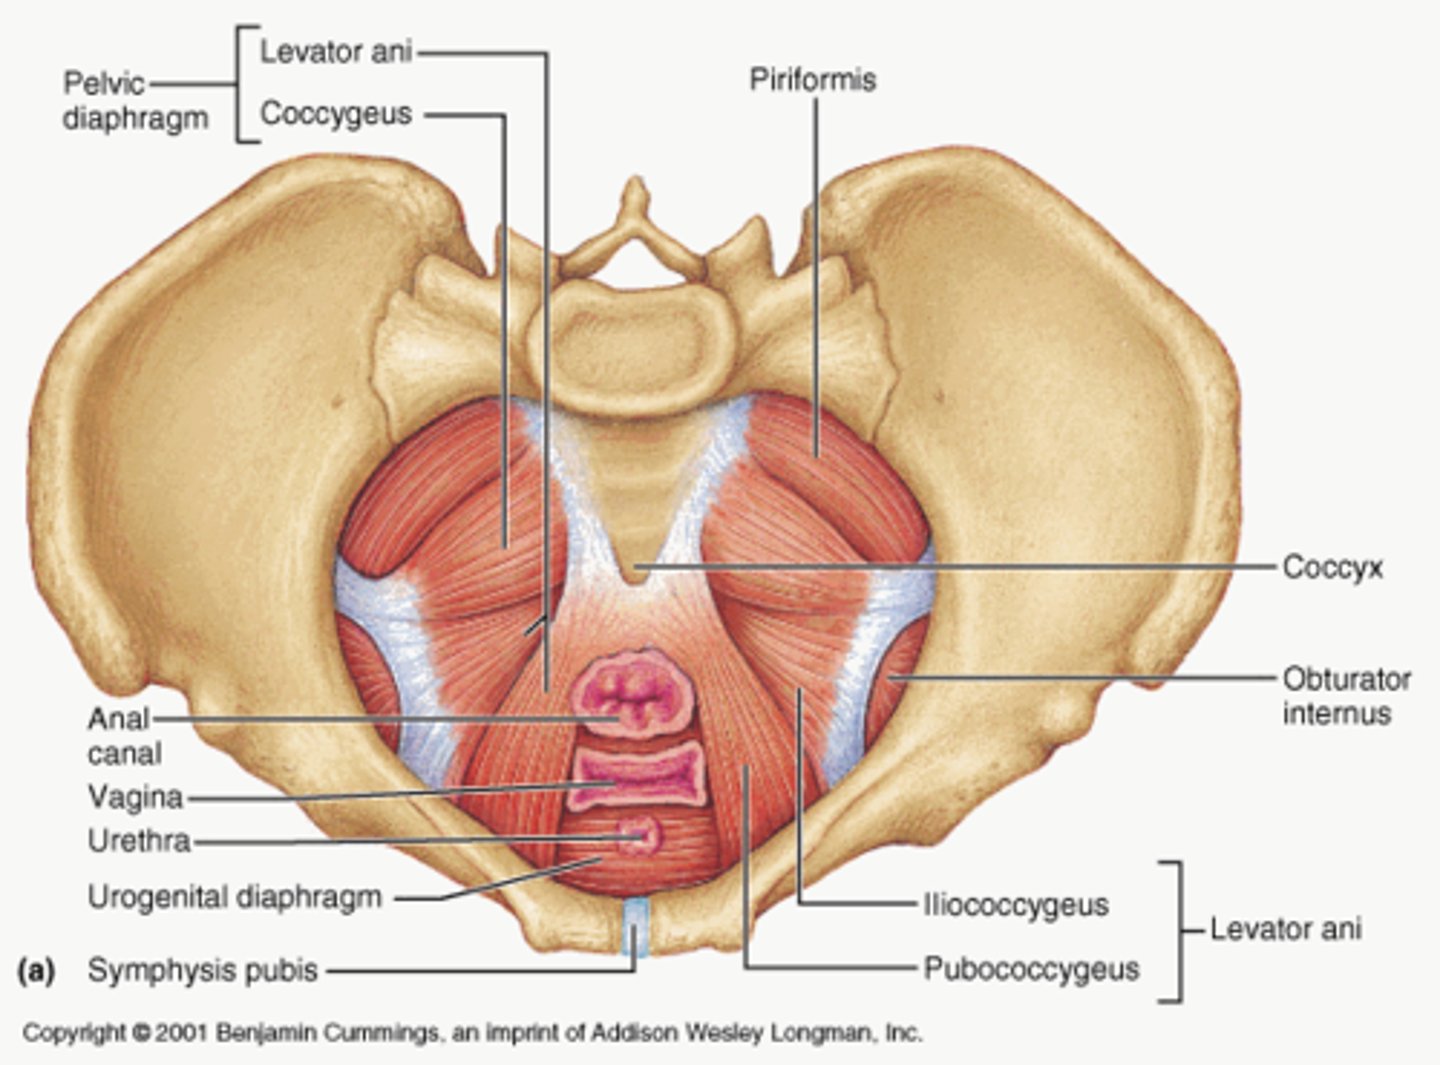

pelvic floor

The muscular base of the abdomen attached to the pelvis, supports pelvic organs, influence urination, defecation, sexual function

levator ani muscles

puborectalis, pubococcygeus, iliococcygeus

urethral canal

lumen of urethra that drains urine from bladder in male and female, and semen from reproductive system in male

hiatuses in pelvic floor

urethral canal, rectal canal, vaginal canal

rectal canal

Most posterior opening in the pelvic floor, bordered by puborectalis

vaginal canal

middle opening in the pelvic floor that allows passage of the fetus during birth

pelvic diaphragm (proper)

levator ani and coccygeus

pelvic diaphragm (all groups)

includes pelvic diaphragm proper, urogenital diaphragm, sphincters and erectile muscles of urogenital tract

Puborectalis

O: anteriorly, from pubic symphysis

I: posteriorly, around anorectal junction

A: inhibits and also aids in defecation, and flatulence

What is the result of damage to puborectalis?

involuntary farting and defecation

Pubococcygeus

O: pubic bone (lateral to puborectalis)

I: coccyx

A: controls urine flow, contracts during orgasm

pelvic floor injury

-extremely common consequence of vaginal delivery

-puborectalis and pubococcygeus are most common muscles damaged, causing incontinence and sexual dysfunction